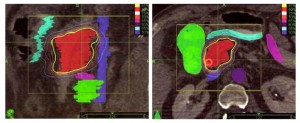

Τα παραδοσιακά συστήματα ακτινοθεραπείας στοχεύουν στη βλάβη από έναν σχετικά μικρό αριθμό σταθερών θέσεων. Αντίθετα, στην ρομποτική ακτινοχειρουργική με CyberKnife® επιλέγονται από το σύστημα εκατοντάδες γωνίες ακτινοβόλησης, που επιλέγονται ανάμεσα σε μερικές χιλιάδες θέσεις που υποστηρίζει το σύστημα. Έτσι έχουμε δυνατότητα να δώσουμε μεγάλες δόσεις θεραπείας στο στόχο στο πάγκρεας, επιβαρύνοντας ελάχιστα τους γύρω φυσιολογικούς ιστούς.